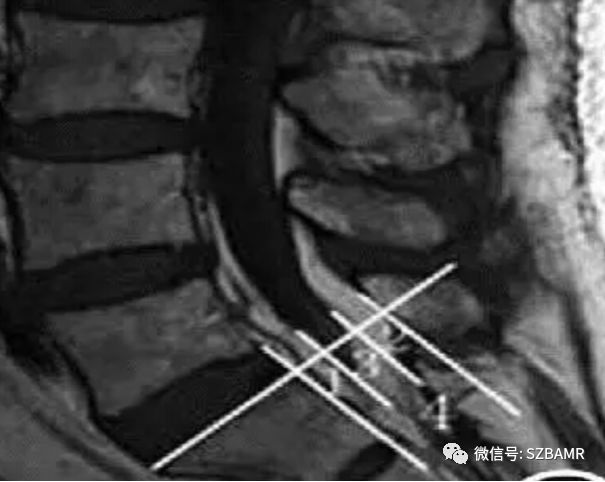

L3/L4 椎间盘水平硬膜囊外背侧脂肪向前突出,呈特征性弧形(红色曲线),1 段表示硬膜囊宽径,2 段表示硬膜外背侧脂肪宽径,可见硬膜囊被压缩变扁。

1为腹侧硬膜外脂肪厚度;2为背侧硬膜外脂肪厚度(1 2=硬膜外脂肪厚度);3为硬膜囊前后径;4为椎管前后径。

(椎管前后径-硬膜囊前后径)/椎管前后径=硬膜外脂肪厚度占管径的比例